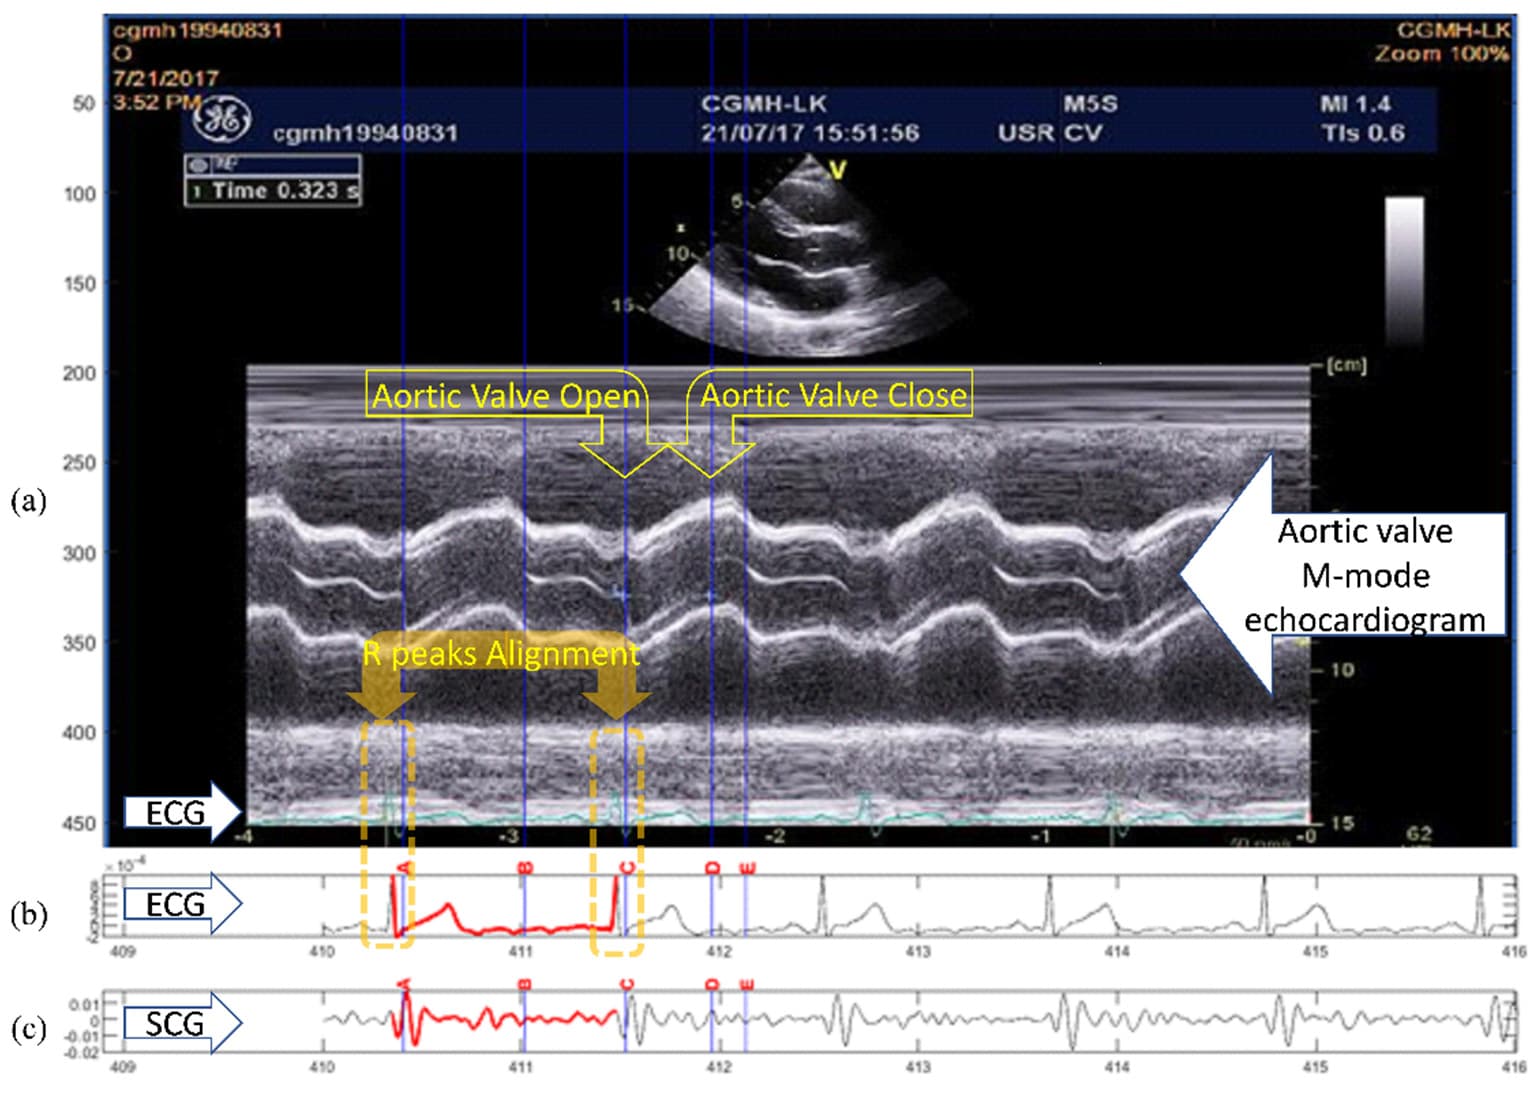

Figure 1. Example of the quasi-synchronous alignment for an echocardiogram image and an SCG measurement: (a) M-mode echocardiogram image of the aortic valve (with an ECG signal at the bottom of the image); (b) ECG signal simultaneously measured with SCG signal; (c) SCG signal.